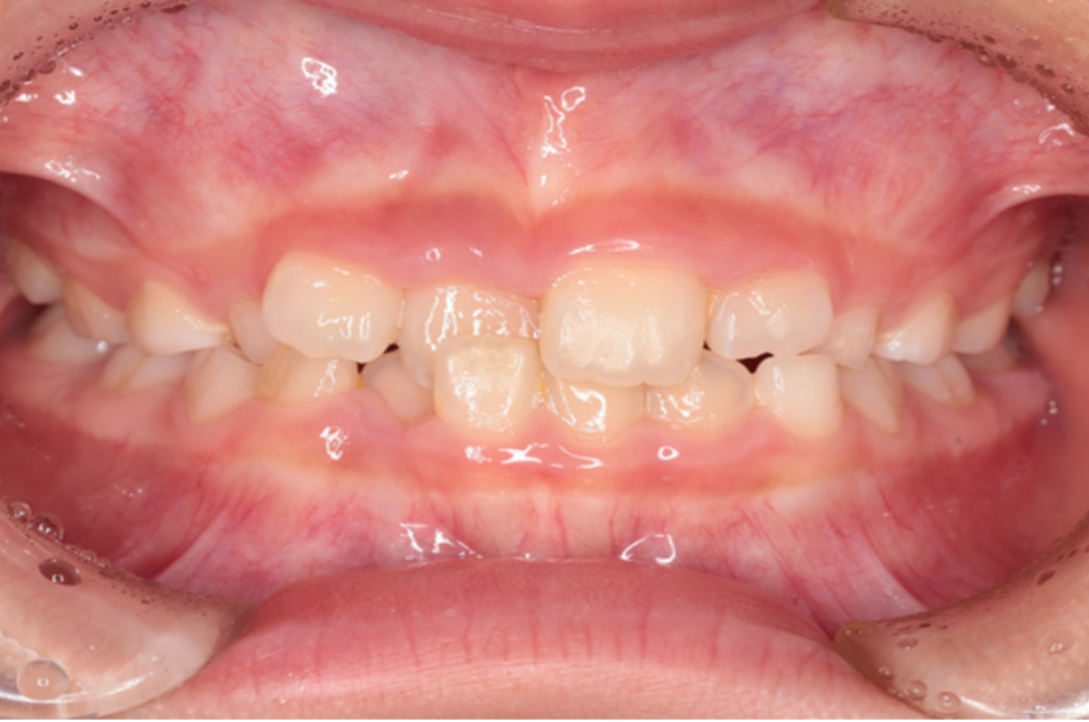

交差している歯並びを改善しました

Under Treatment